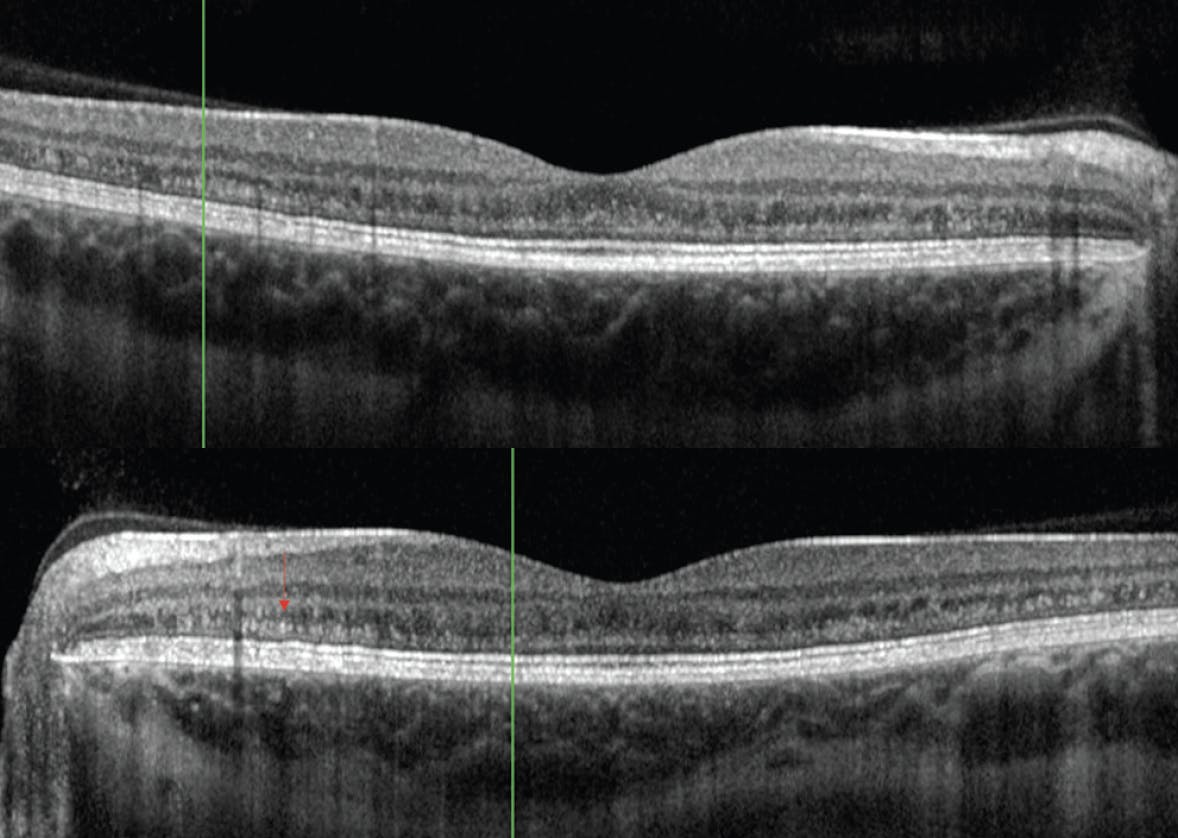

A young adult woman was referred in the setting of abnormal retinal findings, although she was asymptomatic. Her last eye examination had been 10 years prior. On initial examination, her BCVA was 20/20 OD and 20/30 OS. Her dilated fundus examination was significant for 360° peripheral retinal hyperpigmentation (Figure 1). OCT imaging revealed outer plexiform deposits in the macula of each eye (Figure 2). Fundus autofluorescence (FAF) showed hypofluorescence in areas of atrophy in the periphery and punctate areas of hyperfluorescence in the areas of the deposits (Figure 3). Visual fields were full bilaterally.

Figure 2. OCT imaging was remarkable for outer plexiform deposits (red arrow) in the macula of each eye.